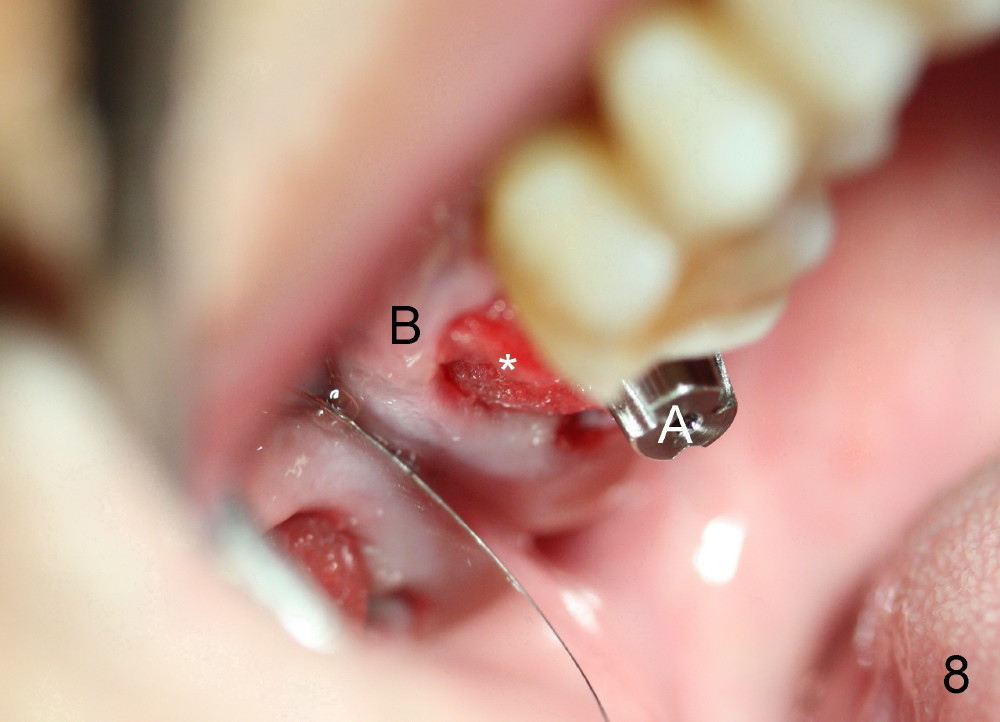

By contrast the palatal socket is deep and relatively small (Fig.4 P), easy to insert taps without drills. When a 7x11 mm tap is placed (Fig.5 T), the coronal end is more or less near the lingual cusps (functional cusps). Although the 7x14 mm tap (Fig.6 T) and a 7x11 mm implant (Fig.7 I) look poking into the maxillary sinus, they are in fact within the palatal socket (Fig.10c). Allograft and Osteogen are placed in the buccal socket (Fig.7 *), followed by collagen dressing (Fig.8 *). A 5x5 mm abutment is placed (Fig.8 A). An immediate provisional (Fig.9 P) is cemented to keep the graft and collagen dressing in place.

The patient returns to clinic 1 month postop, because of loosening of the provisional. The buccal socket appears to have epithelium (Fig.11 B); the keratinized gingiva has apparently moved (arrow) to cover the buccal surface of the implant (I). The long abutment, which was used for retention of the immediate provisional as well as the graft and collagen dressing, has finished its mission. It is changed to a shorter one to accommodate the future occlusion. A second implant is planned to be placed at the site of #31.